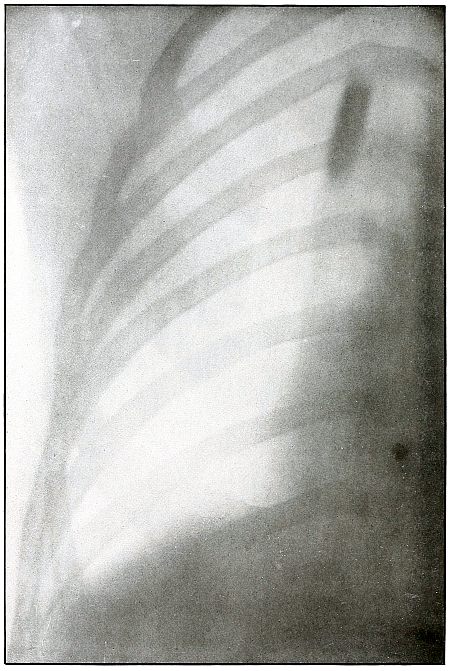

CHEST.

Plate 45.

[Pg 101]

Rifle—Plate 45.

CHEST.

Penetrating Gunshot Wound of the Chest,

with Lodgment of the Projectile Near Posterior Chest Wall.

Point of entrance, pectoral border and fourth rib.

Point of exit, none.

The distinct shadow of the angle of the ribs shows that the posterior

chest wall was next to the photographic plate, and that the larger and

less distinct outline of the anterior portions of the upper ribs was

farther from the plate.

The nearly normal size of the shadow of the projectile shows it to be

much nearer the posterior than the anterior chest wall. The blurred

outline shows it to have moved with respiration. Such conditions

locate its position within the thoracic cavity.

The emergency treatment is antiseptic dressing and rest.

The subsequent treatment depends upon pleural involvement or the

extremely rare infection of the lung.

These cases are nearly all aseptic, and if the great vessels and

nerves of the chest escape injury results are generally favorable.